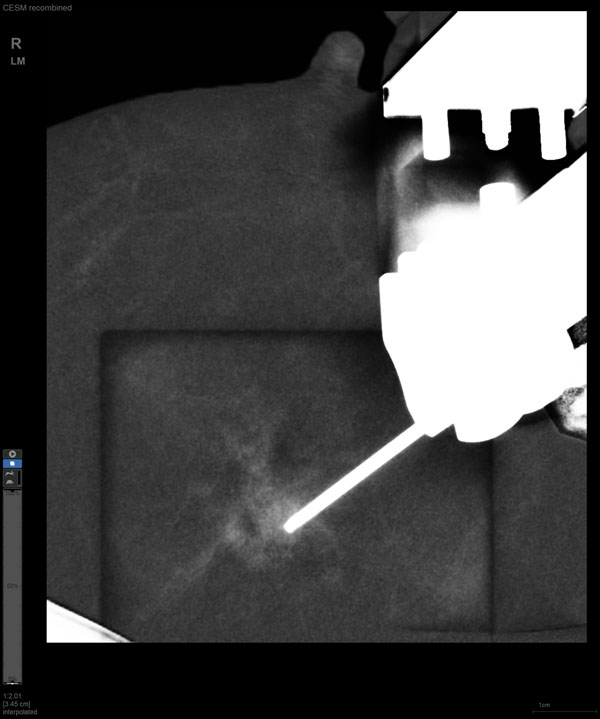

CEM引导下穿刺

某患者增强磁共振成像MRI显示肿瘤周边有活性,中心区域有组织坏死。为得到准确的病理结果,穿刺靶区需避开肿物坏死区域。在与患者主管医生充分讨论后,放射科医生为患者行CEM引导下穿刺活检术。术中,CEM检查肿物同样显示为环形强化,巧妙避开坏死区域后,穿刺靶区选择了肿物增强早期明显强化区域,术程顺利,仅用时15分钟。术后该患者病理结果为浸润性导管癌Ⅱ级。